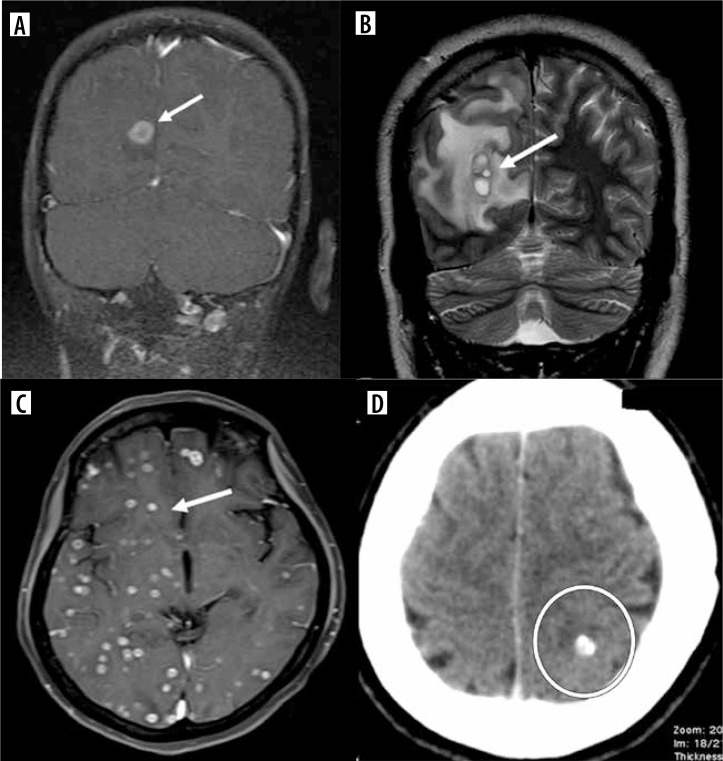

目的:探讨实质性神经囊虫病(NCC)独特的影像学特征,有助于与其他疾病鉴别。材料和方法:根据头节的鉴定选择250例NCC患者。进行T2加权、T1流体衰减反演恢复(FLAIR)、T2 FLAIR、磁化率加权成像、稳态构造干涉、扩散加权成像和T1加权对比序列。分析囊肿各阶段的影像学特征。结果:本研究提出了以前未记载的NCC的影像学表现,建立了基于磁共振成像特征的绝对、主要和次要诊断标准。结论:根据本研究的序列,利用影像学标准诊断NCC,可有效缩小鉴别诊断范围,准确识别。

Purpose: To study the distinct imaging characteristics of parenchymal neurocysticercosis (NCC) that aid in distinguishing it from other diseases.

Material and methods: Two hundred fifty patients with NCC were selected based on identification of the scolex. T2 weighted, T1 fluid attenuated inversion recovery (FLAIR), T2 FLAIR, susceptibility weighted imaging, constructive interference in steady state, diffusion weighted imaging, and T1 weighted contrast sequences were performed. The imaging characteristics of the cysts at various stages were analyzed.

Results: This study presents previously undocumented imaging findings of NCC, establishing absolute, major, and minor criteria for its diagnosis based on magnetic resonance imaging features.

Conclusions: Utilizing imaging criteria for diagnosing NCC, as per the study's sequences, can effectively narrow down differential diagnoses and lead to accurate identification.